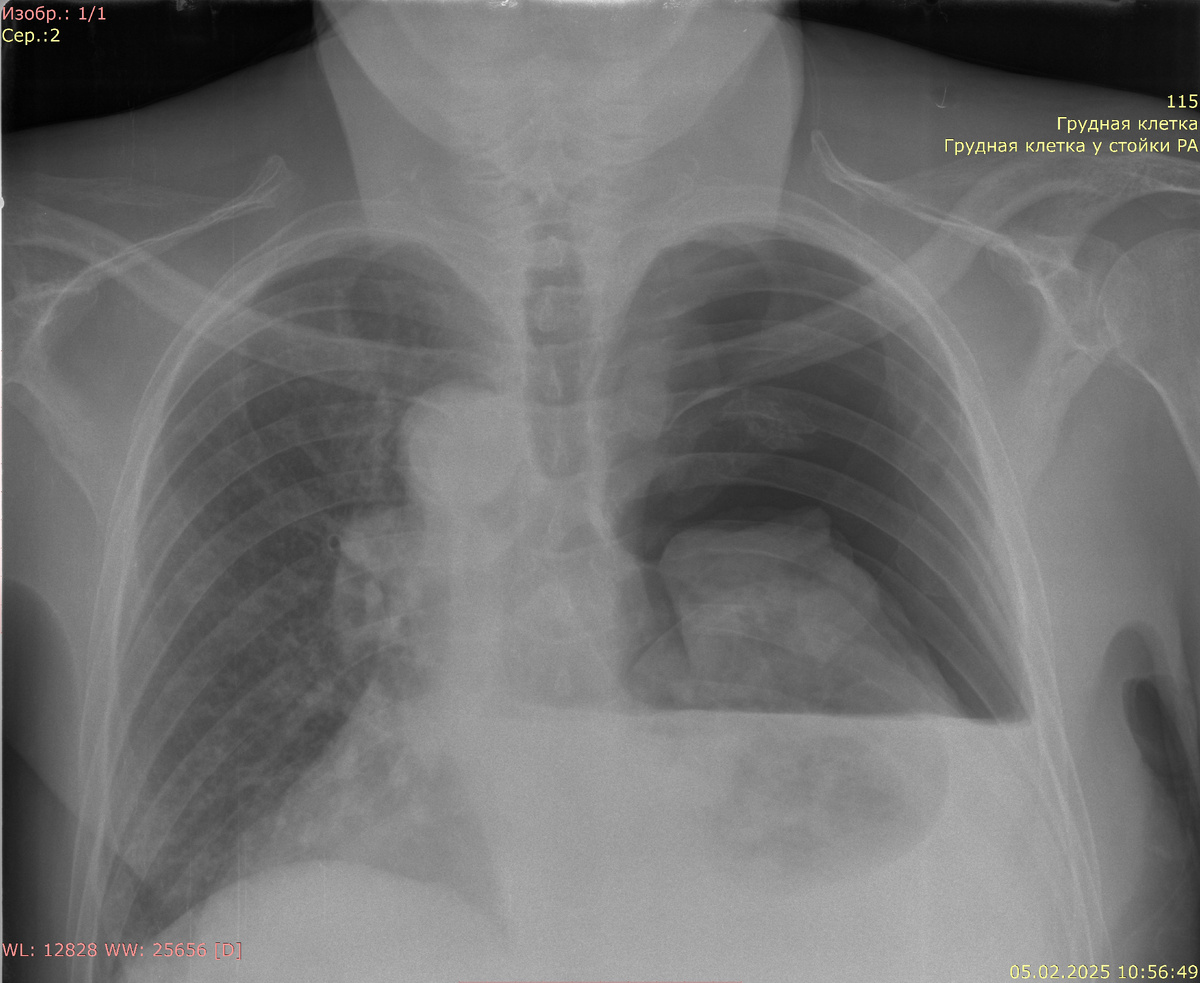

Рентгенография органов грудной клетки в прямой проекции:

Видимые дыхательные пути проходимы. Тень средостения смещена влево, не расширена. Корни легких четкие, структурные, не расширены. Правое легкое коллабировано на 2/3, аваскулярная зона справа до 100 мм. Горизонтальная гомогенная тень плеврального выпота справа до 3 м/р по среднеключичной линии. Усиление легочного рисунка в левом легком. Костно-деструктивных изменений нет.

Заключение: правосторонний пневмоторакс. Правосторонний плевральный выпот